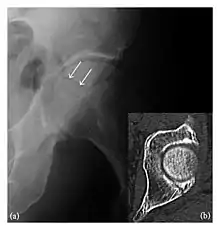

The greater tuberosity of the humerus is also an illustrative location of occult fractures. The osseous injury may follow seizures, glenohumeral dislocation, forced abduction, or direct impaction. They are commonly discovered on MRI in symptomatic patients with suspicion of rotator cuff tear. Coronal images are best suited for detection. They appear as crescentic oblique lines surrounded by a bone marrow edema pattern (Figure 5). The rotator cuff must be inspected since associated ligamentous lesions are common. In the ankle, malleoli and tarsal bones should be checked carefully for any cortical disruptions and radiolucent lines that may reveal a fracture. Awareness of the exact location of the pain will help direct the attention of the interpreter when searching for very subtle signs of fracture (Figure 6).[1]

a

b

Figure 6: Subtle anterior talar fracture in a 39-year-old man presenting with ankle pain after a fall. (a) Anteroposterior radiograph shows a subtle oblique radiolucent line through the talus (white arrows). (b) Sagittal CT reformation confirms the presence of an anterior talar fracture with cortical offset (black arrow). Avulsion fractures, which consist of a detached bone fragment resulting from a ligament or tendon pulling away from the bone, may also present with subtle radiographic signs. Tiny osseous fragments near the presumed attachment site of a ligament suggest this diagnosis. Common sites are the lateral tibial plateau (the Segond fracture), the spinal tuberosity of the tibia resulting from anterior cruciate ligament avulsion, and the ischial tuberosity.[1]